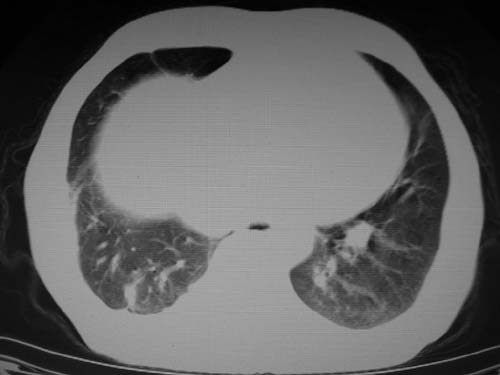

男,80岁

1)考虑肺动脉狭窄。2)右肺上叶继发性肺结核。3)右侧胸膜增厚、钙化,左侧胸膜反应。

左肺动脉异常增粗,考虑肺动脉狭窄可能。

右肺上叶继发性肺结核。

右侧胸膜增厚、钙化,左侧胸膜反应。

双肺陈旧性病变,左肺动脉高压.

1)考虑左肺动脉瘤可能性大,建议增强。2)右肺上叶继发性肺结核。3)右侧胸膜增厚、钙化,左侧胸膜反应。

)考虑肺动脉扩张,右心室增大,主动脉弓段正常位弓后段明显变小(不会是动脉导客未闭吧,不知患者有何症状病史)0。2)右肺上叶继发性肺结核。3)右侧胸膜增厚、钙化,左侧胸膜反应。

结合患者年龄,不除外左下肺扩张性动脉瘤,建议胸透是否有扩张性博动,以便确诊。

肺动脉高压,左肺动脉瘤样扩张。